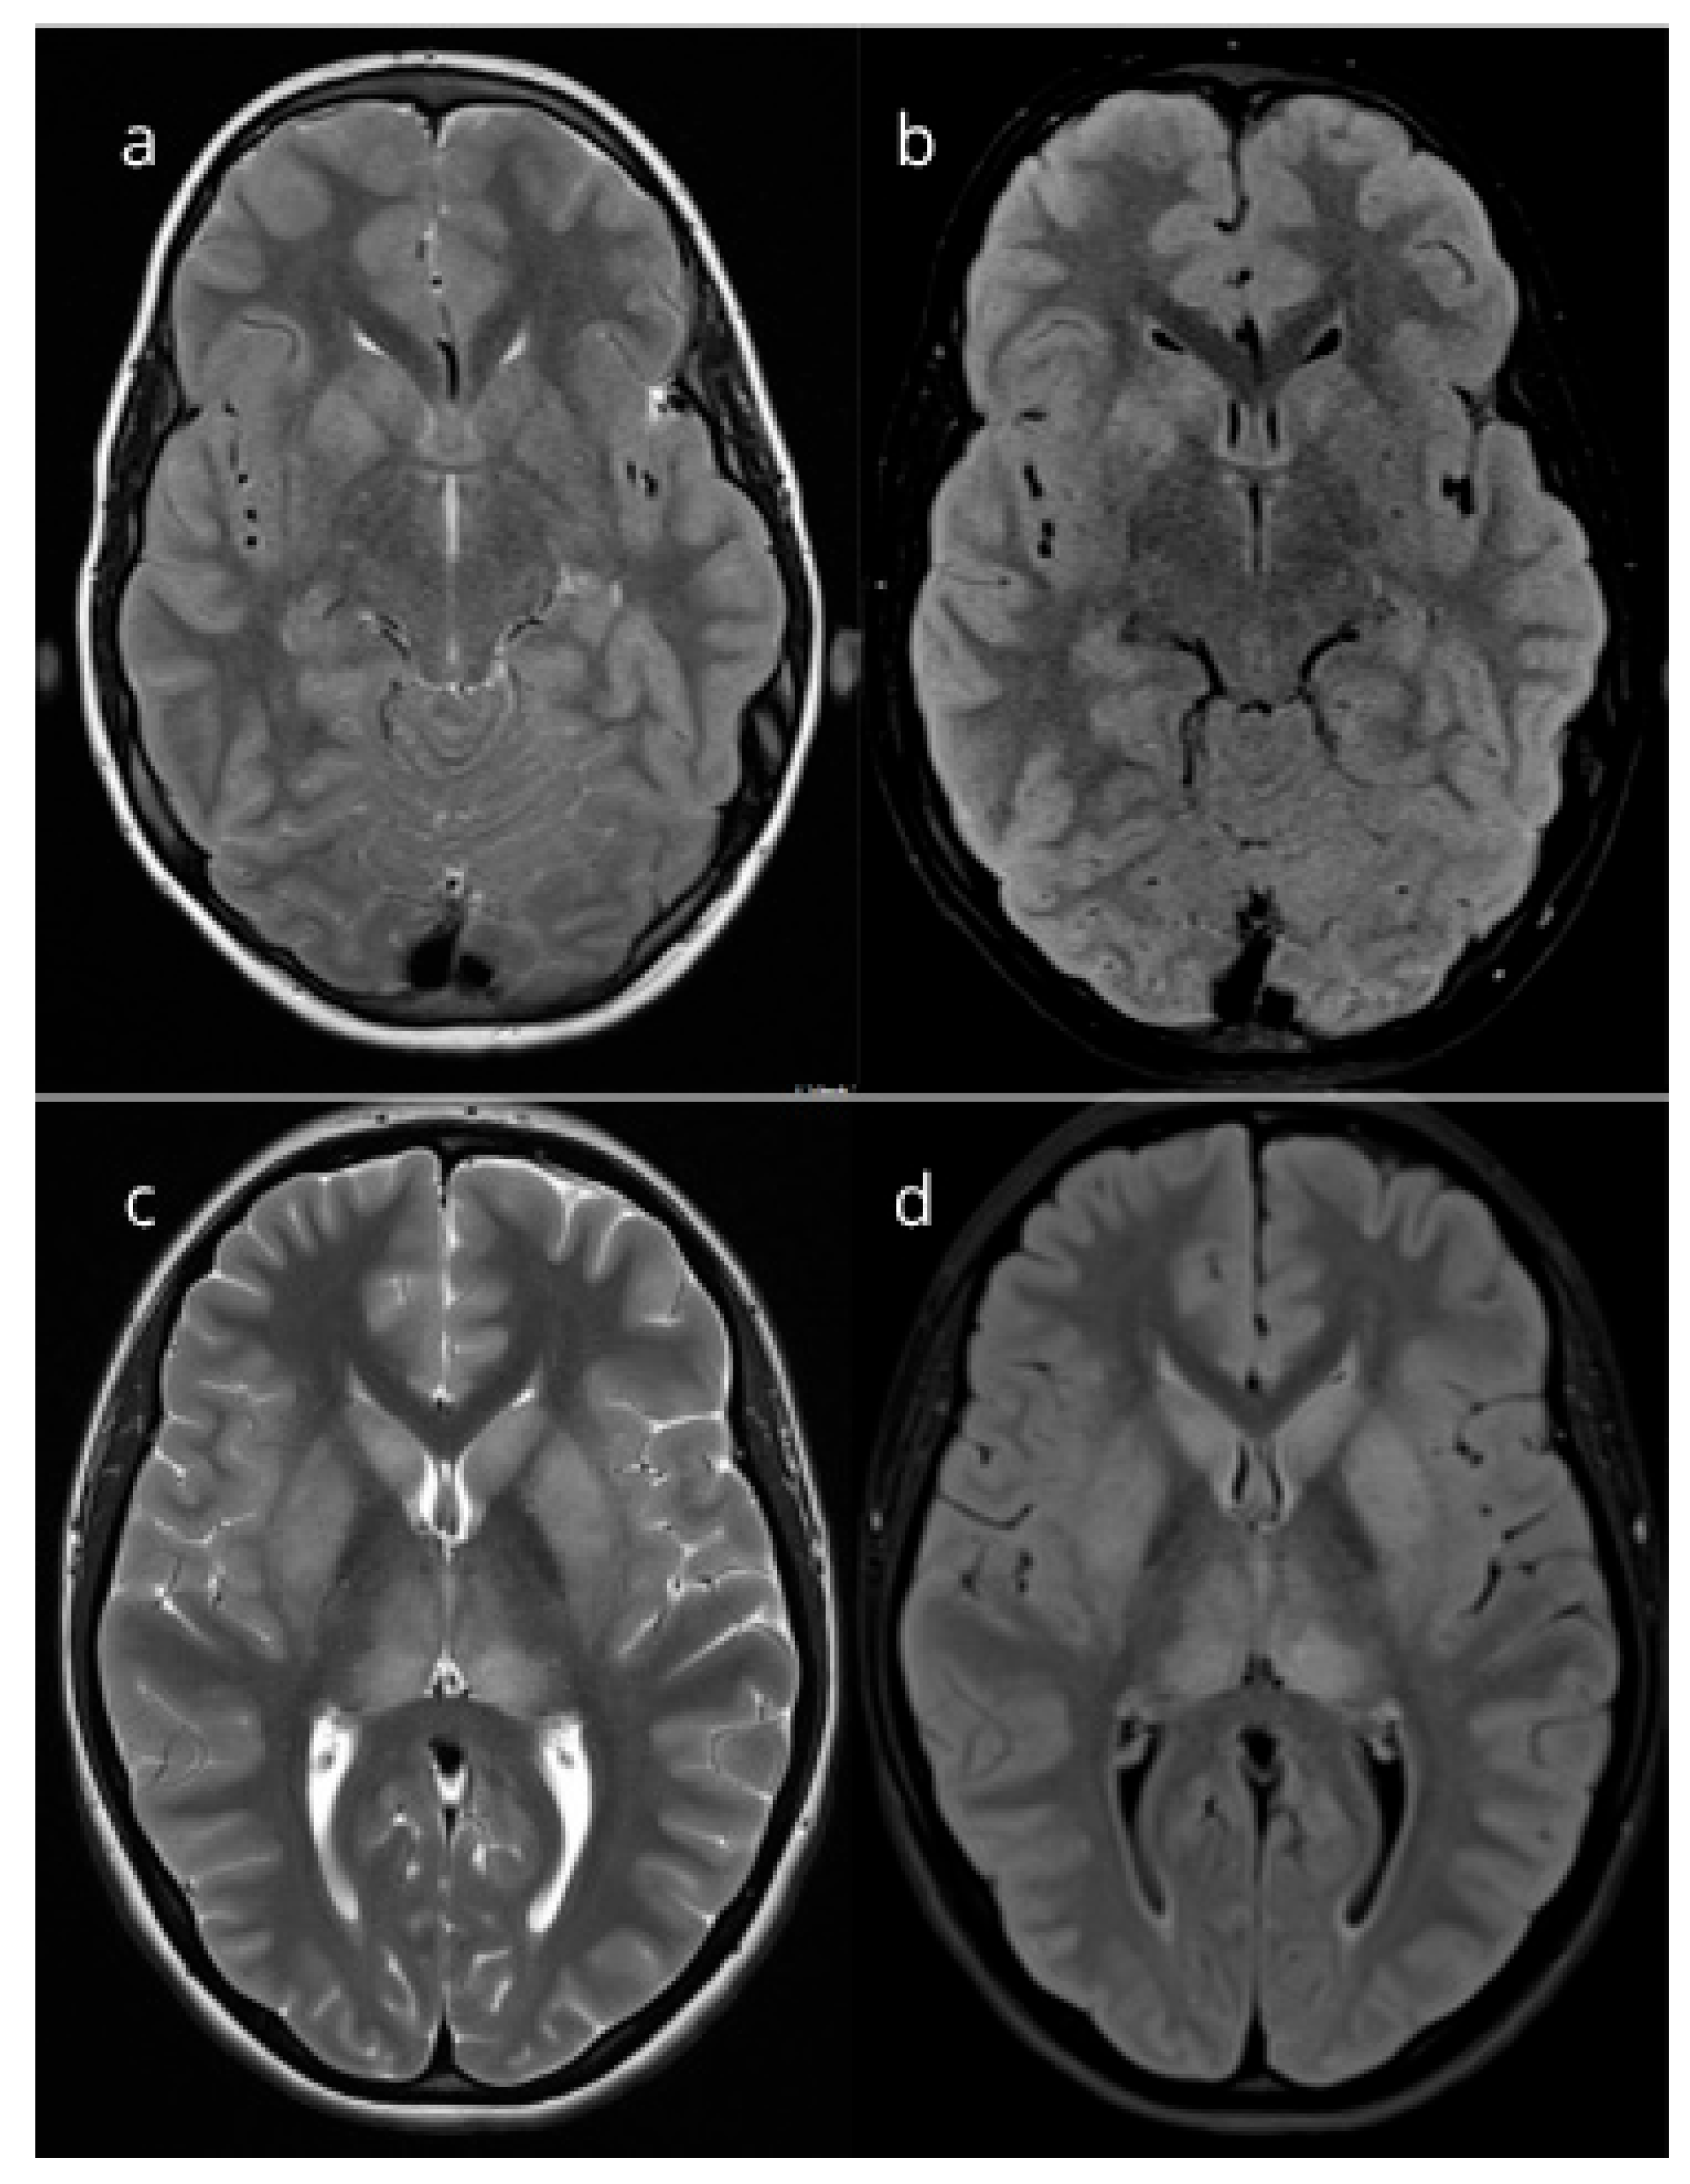

| Patient 1 | M | 11 years and 9 months | 331 | 44 | 56 | 0.78 | T2-weighted and FLAIR images demonstrate bilaterally asymmetrical high signal intensity in the caudate nuclei, ventral portions of the globus pallidus, and putamina. A linear area of increased signal extends toward the right half of the hypothalamus. A Chiari I malformation is also noted. | Methylprednisolone (doses of 2.5 mg/kg/day for 5 days, followed by taper-off) | Full recovery |

| Patient 2 | F | 14 years and 2 months | 480 | 15 | 85 | 1.21 | T2-weighted and FLAIR images demonstrate bilaterally symmetrical high signal intensity in the thalami (pulvinar nuclei), caudate nuclei, and putamina, findings consistent with encephalitis. | Methylprednisolone (doses of 2.5 mg/kg/day for 5 days, followed by taper-off) | Full recovery |